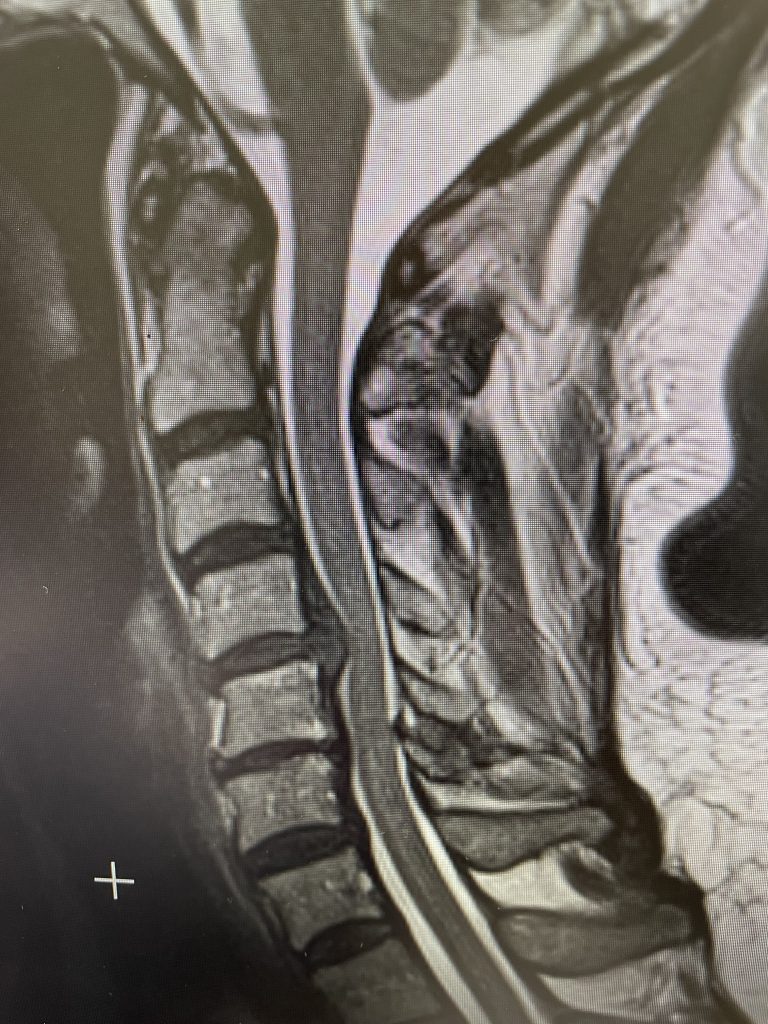

IMG 4807 scaled

This 52 year-old female presents with 4 months of progressive neck pain, numbness of both hands, and difficulty using her hands and buttoning a shirt. She was noted to have mild right-sided weakness in a long track distribution which included her finger extensor, hip flexor, dorsiflexor weakness. She had tried chiropractic care. Imaging revealed a very large C4-5 disc herniation with severe cord compression which was more eccentric to the right, but also causing left-sided compression (Fig 1). The patient also had C5-6 disc collapse with biomechanical reduction of the C5-6 motion segment which puts more stress on the next segment. In essence the C5-6 is acting like it is autofused. This resulted in premature degeneration of the C4-5 segment which resulted in the disc herniation. It was decided, given a diagnosis of early cervical myelopathy with spinal cord compression, to offer an anterior cervical discectomy and fusion at C4-5 to decompress the spinal cord.